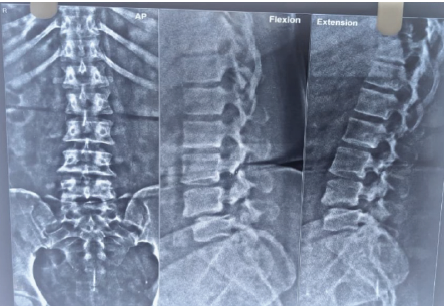

X-ray suggested-

– Grade III anterior spondylolisthesis of L4 on L5 with 50% slippage

– Grade II anterior spondylolisthesis of L3 on L4 (Figure 1)